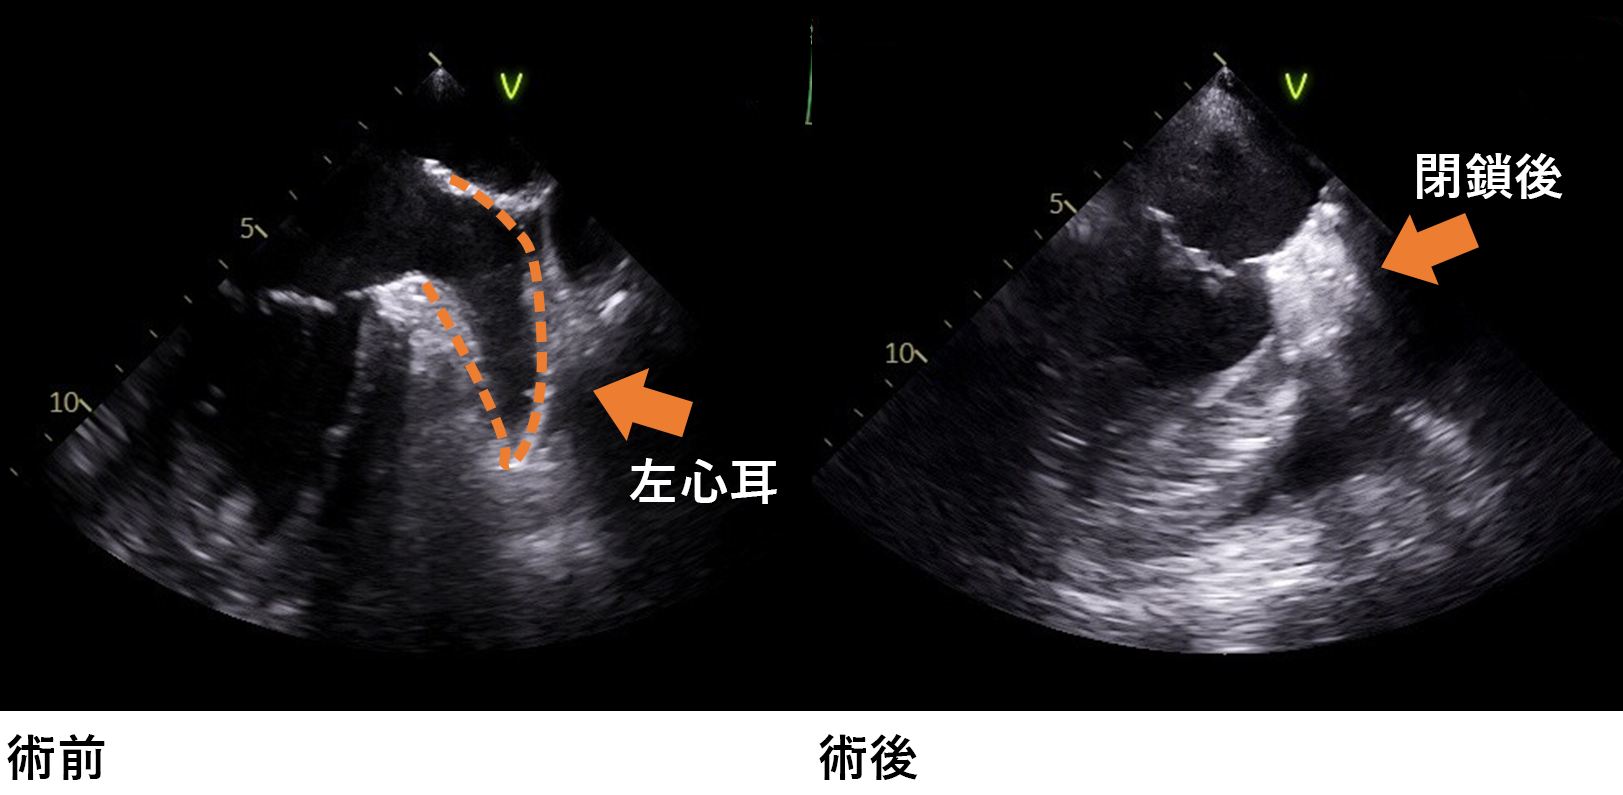

・慢性心房細動で抗凝固療法が難しい患者様に対しては左小開胸で左心耳閉鎖術を行っています。